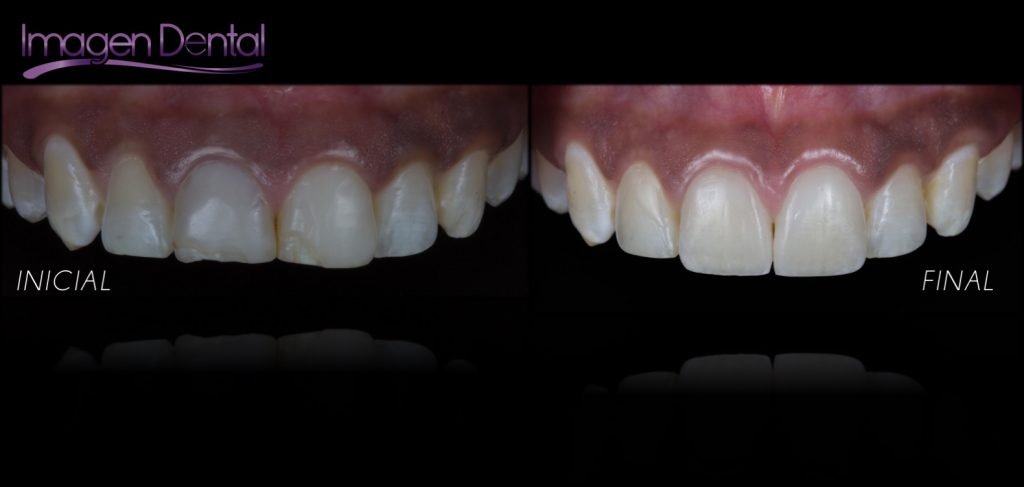

Punto Bajío Casos Clínicos Prótesis Fija sobre Implante unitario Inicio Provisional Final Prótesis Parcial Fija sobre 2 Implantes 2 Implantes Final Prótesis Bucal Removible Inicial Inicial Superior Inicial Inferior Rayos X Inicial Rayos X Inicial Frontal Final Final Superior Final Inferior Prótesis Parcial Fija/ Coronas de Circonio Sonrisa Inicial Foto Inicial Foto Inicial Inferior Foto Final Inferior Foto Final Sonrisa Final Prótesis Total Protesis Inmediatas 1 Protesis Inmediatas 2 Prótesis Removible/ Coronas Metal-Ceramica Carillas Incrustaciones Endodoncia